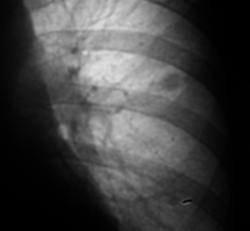

Провели дообследование.

А ещё смущает некоторое неоднородность, даже какие то плотные включения, межет это конечно сосуды накладываются.  Валентин Львович, у Вас же наверное где то томограмка завалялась?

А плотные включения все таки есть.

Могу ошибаться, но сдесь включения есть.

Всмысле на 27 снимке.

А я и не возражаю по поводу включений, да и локализация, да и "дорожка", по всей видимости оказалась "эфимерой", но вот вопрос - "куда направить"?